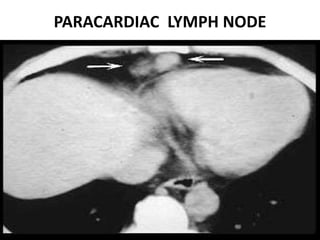

PARACARDIAC LYMPH NODE